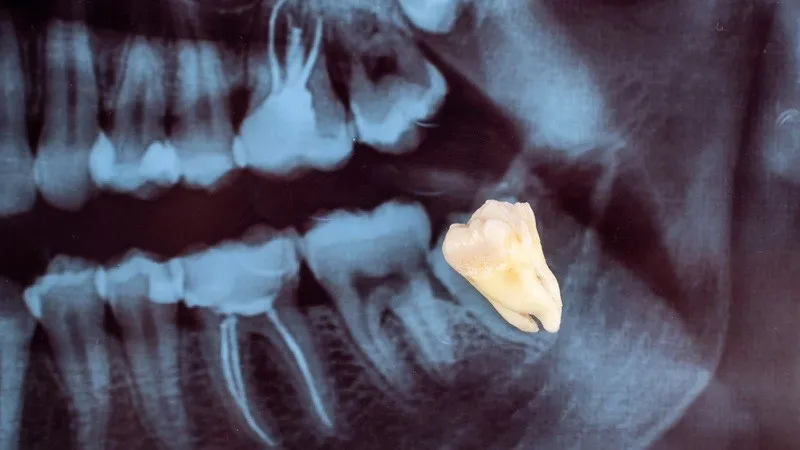

Đây là tình trạng khi một chiếc răng không thể mọc lên hoàn toàn để lộ ra ngoài bề mặt nướu, mà bị kẹt lại trong xương hàm hoặc mô mềm xung quanh. Điều này thường xảy ra khi không đủ không gian trong cung hàm để răng phát triển hoặc do răng bị lệch hướng trong quá trình mọc.

Tình trạng này phổ biến nhất ở răng khôn (răng số 8), nhưng cũng có thể xảy ra ở các răng khác như răng nanh hay răng hàm nhỏ. Răng mọc ngầm không chỉ gây đau nhức mà còn tiềm ẩn nhiều nguy cơ như viêm nhiễm, hư hại các răng lân cận hoặc làm thay đổi cấu trúc hàm.